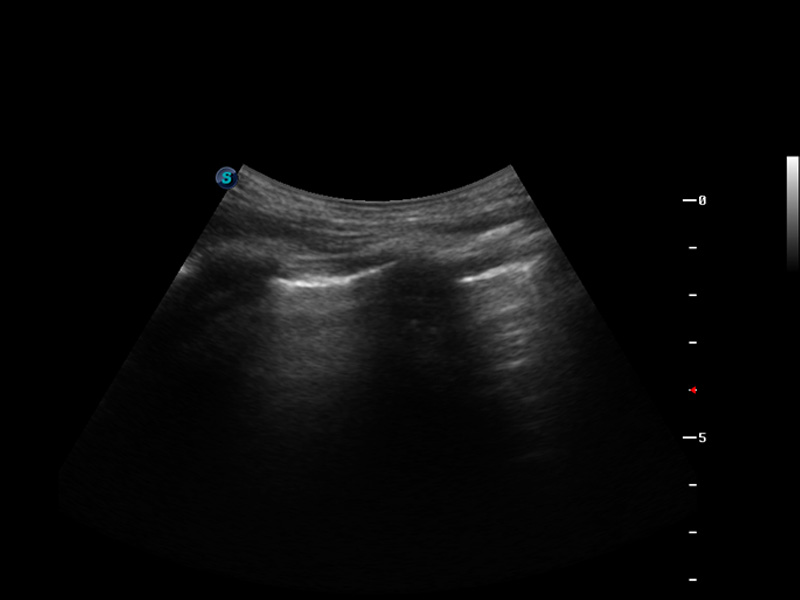

实时宽景成像